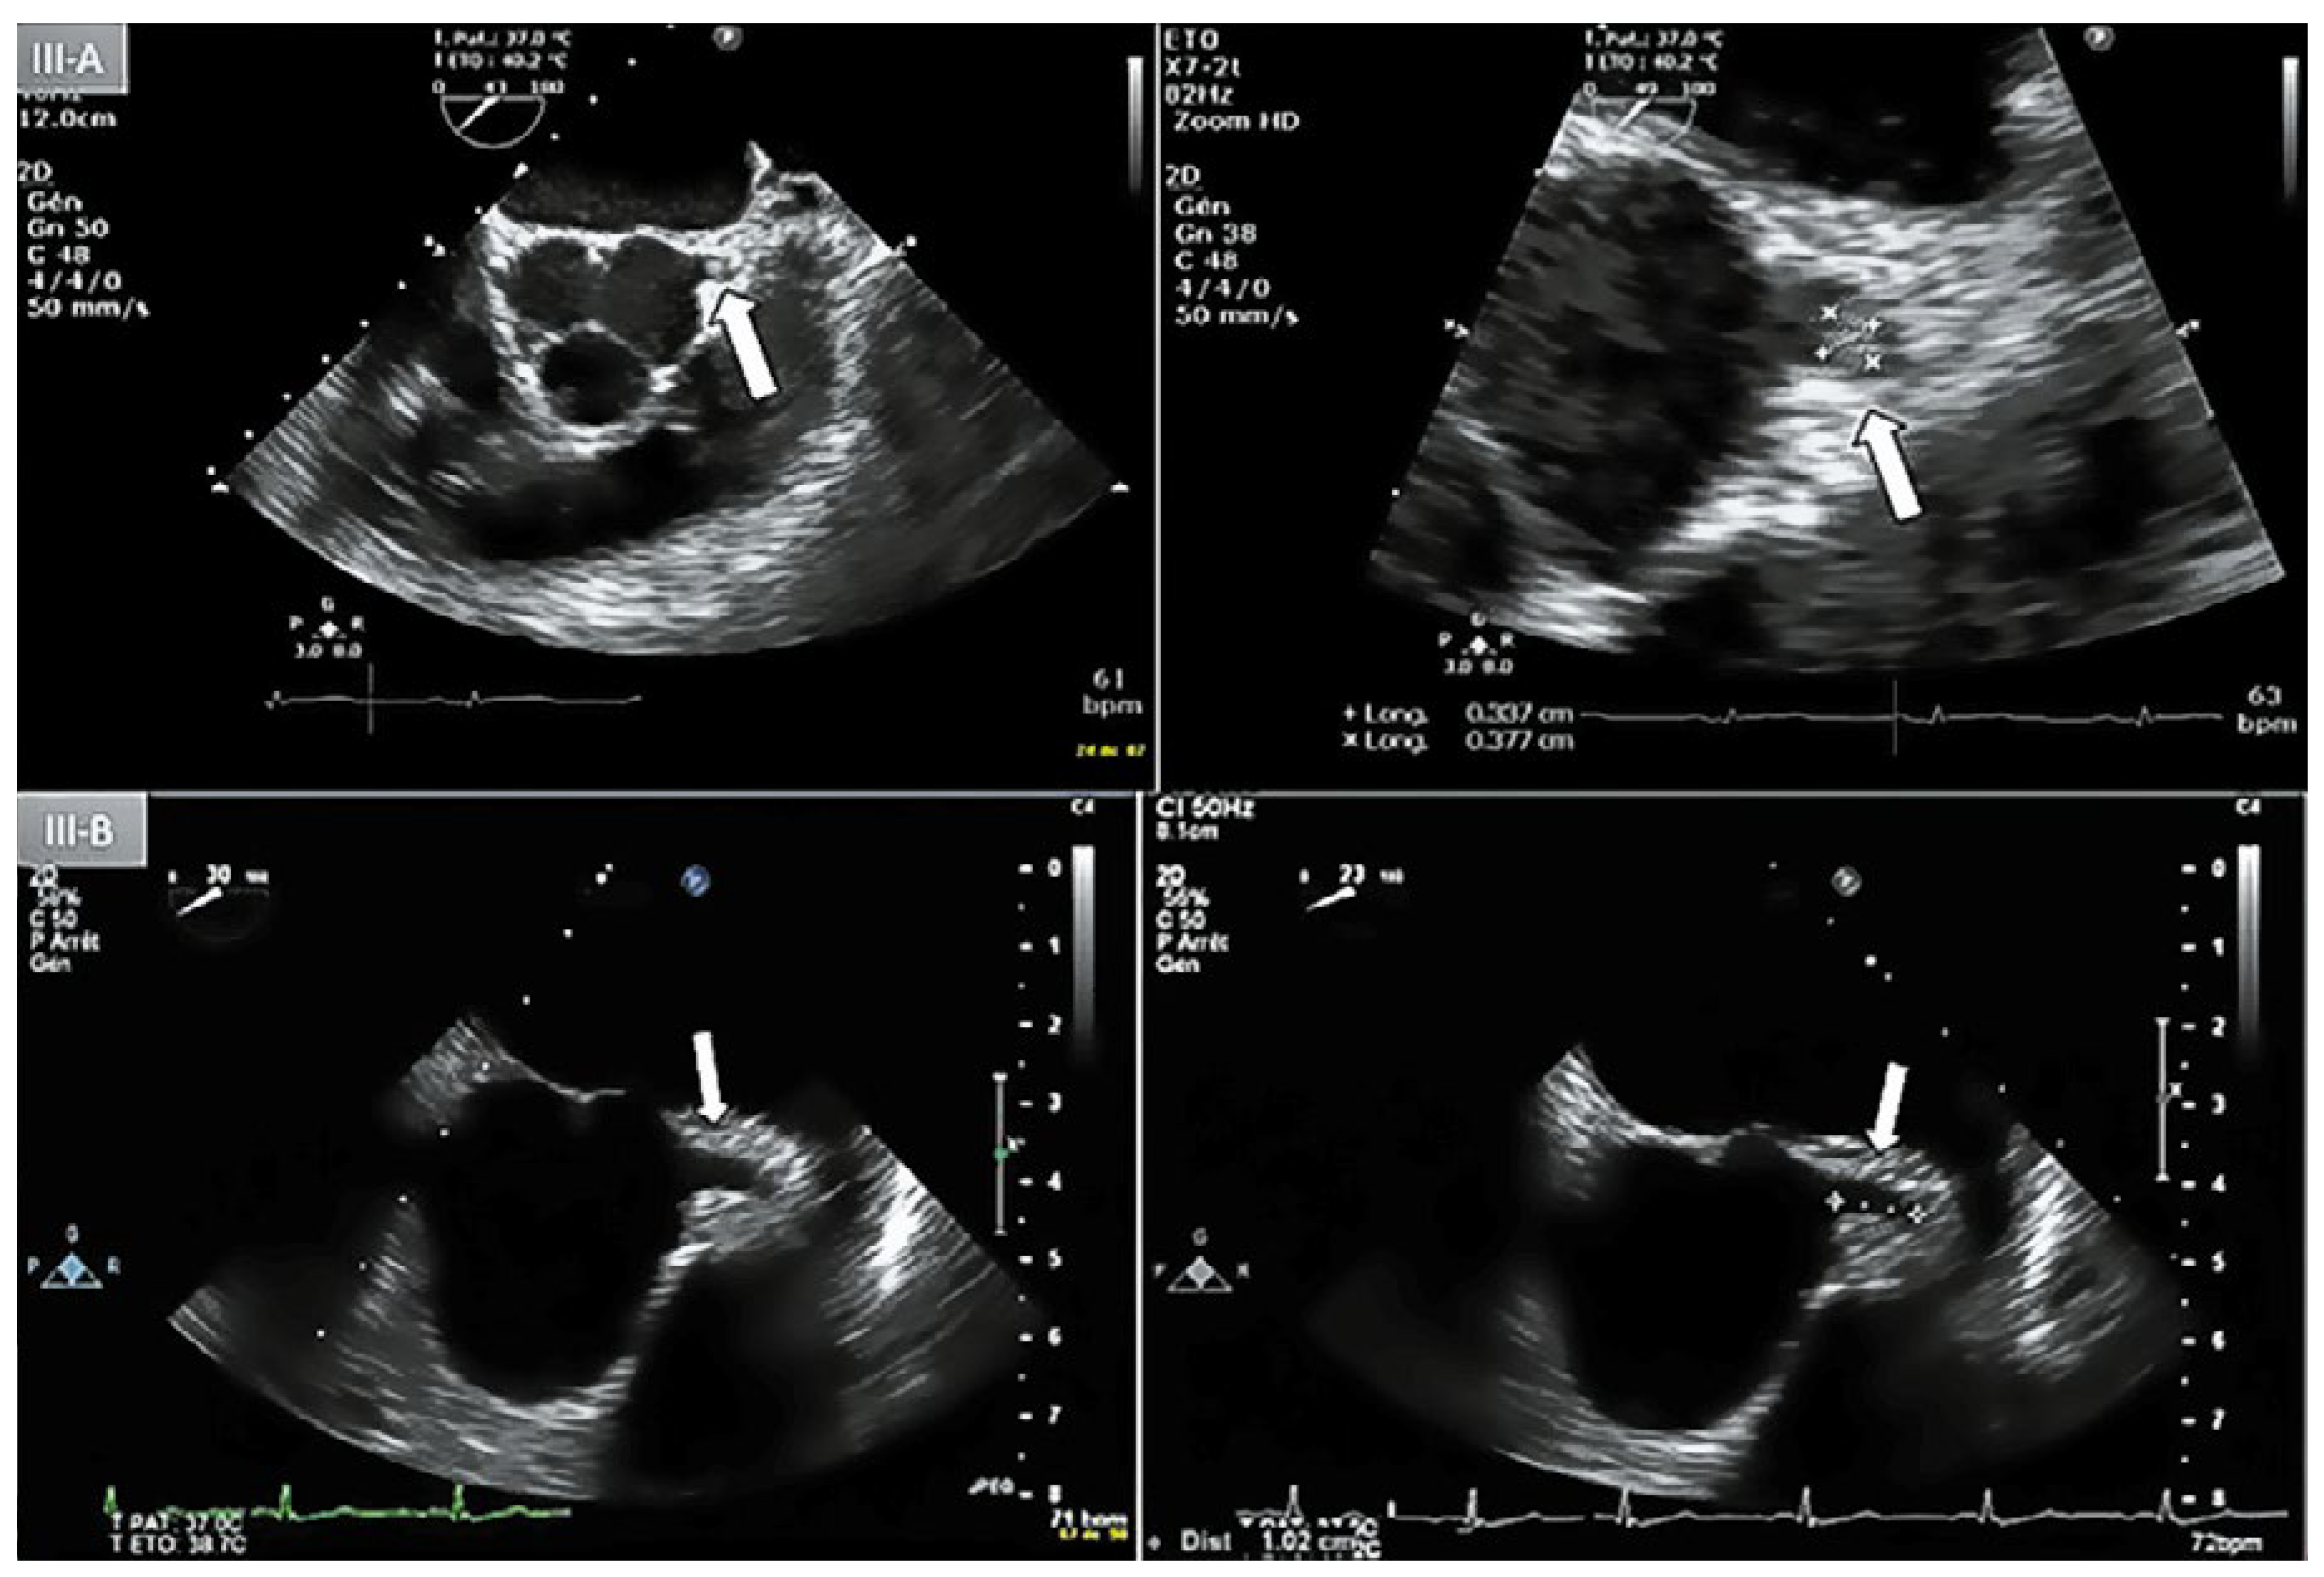

Case report